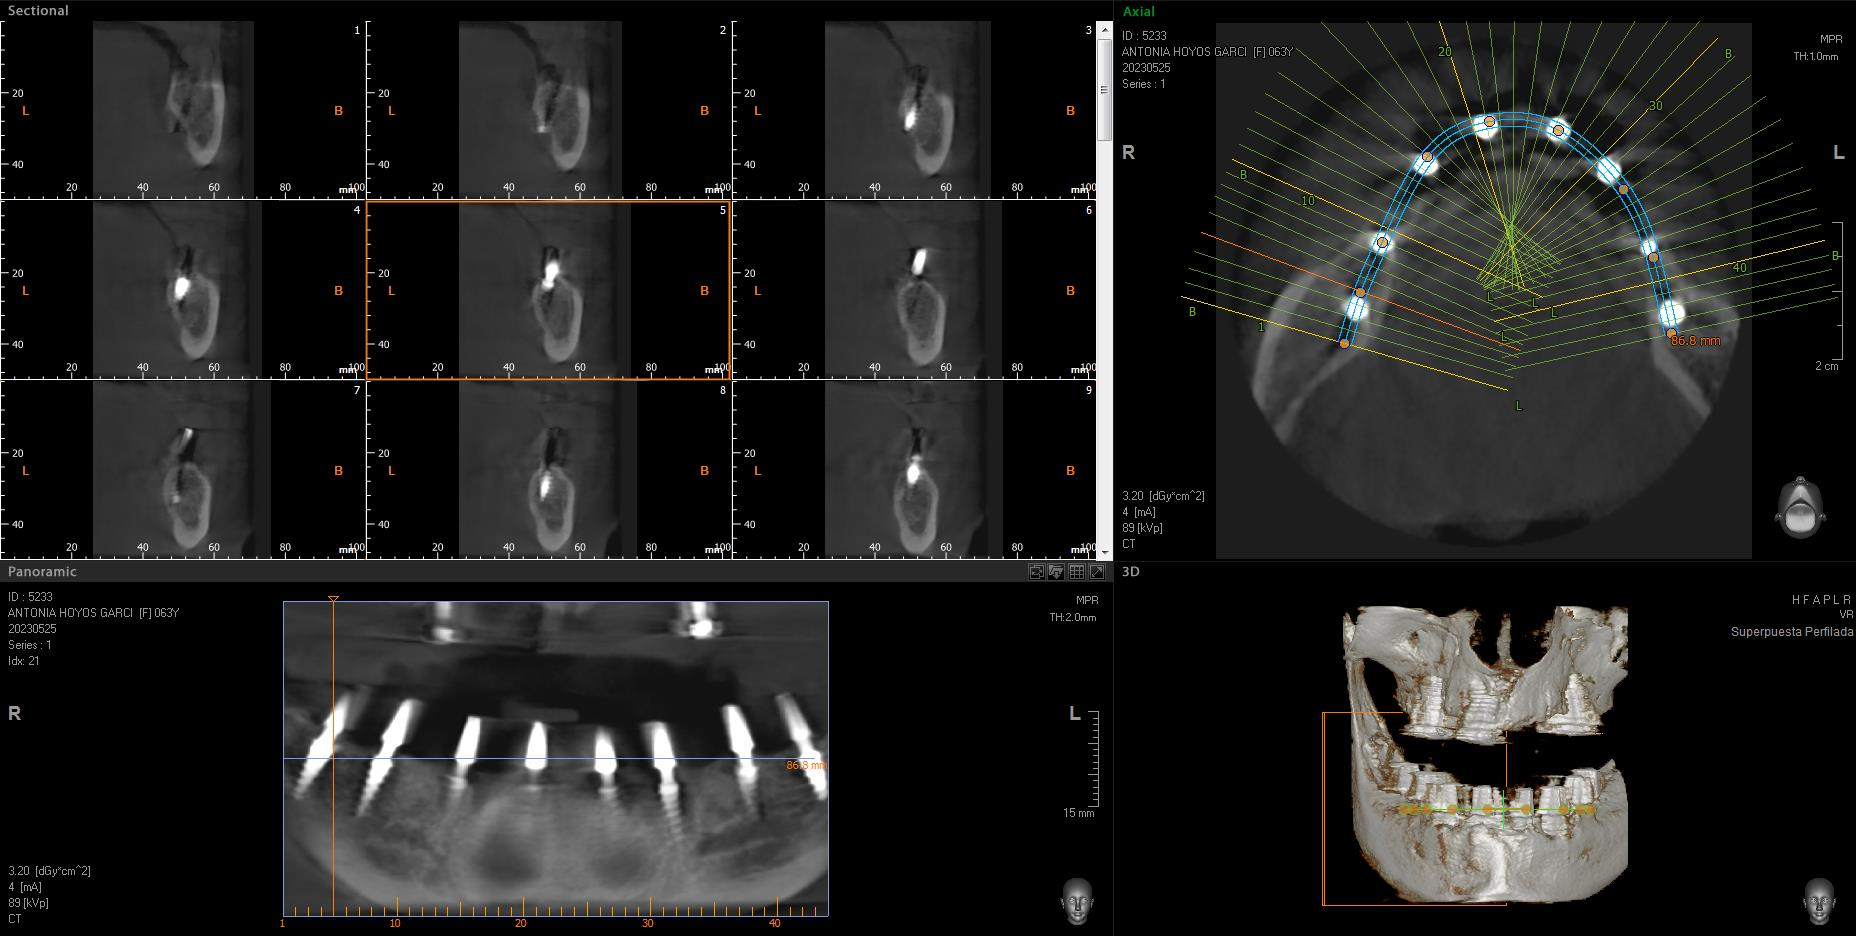

Implantes SLD-c

Secuencia de imágenes RX, antes y después de la inserción de implantes SLD-c en la parte inferior de la boca.

Paciente mujer de 65 años.

- Radiografía previa a la operación.

- Colocación implantes Radhex SLD-c parte inferior.

- Colocación implantes Radhex SLD-c parte inferior con soldadura.